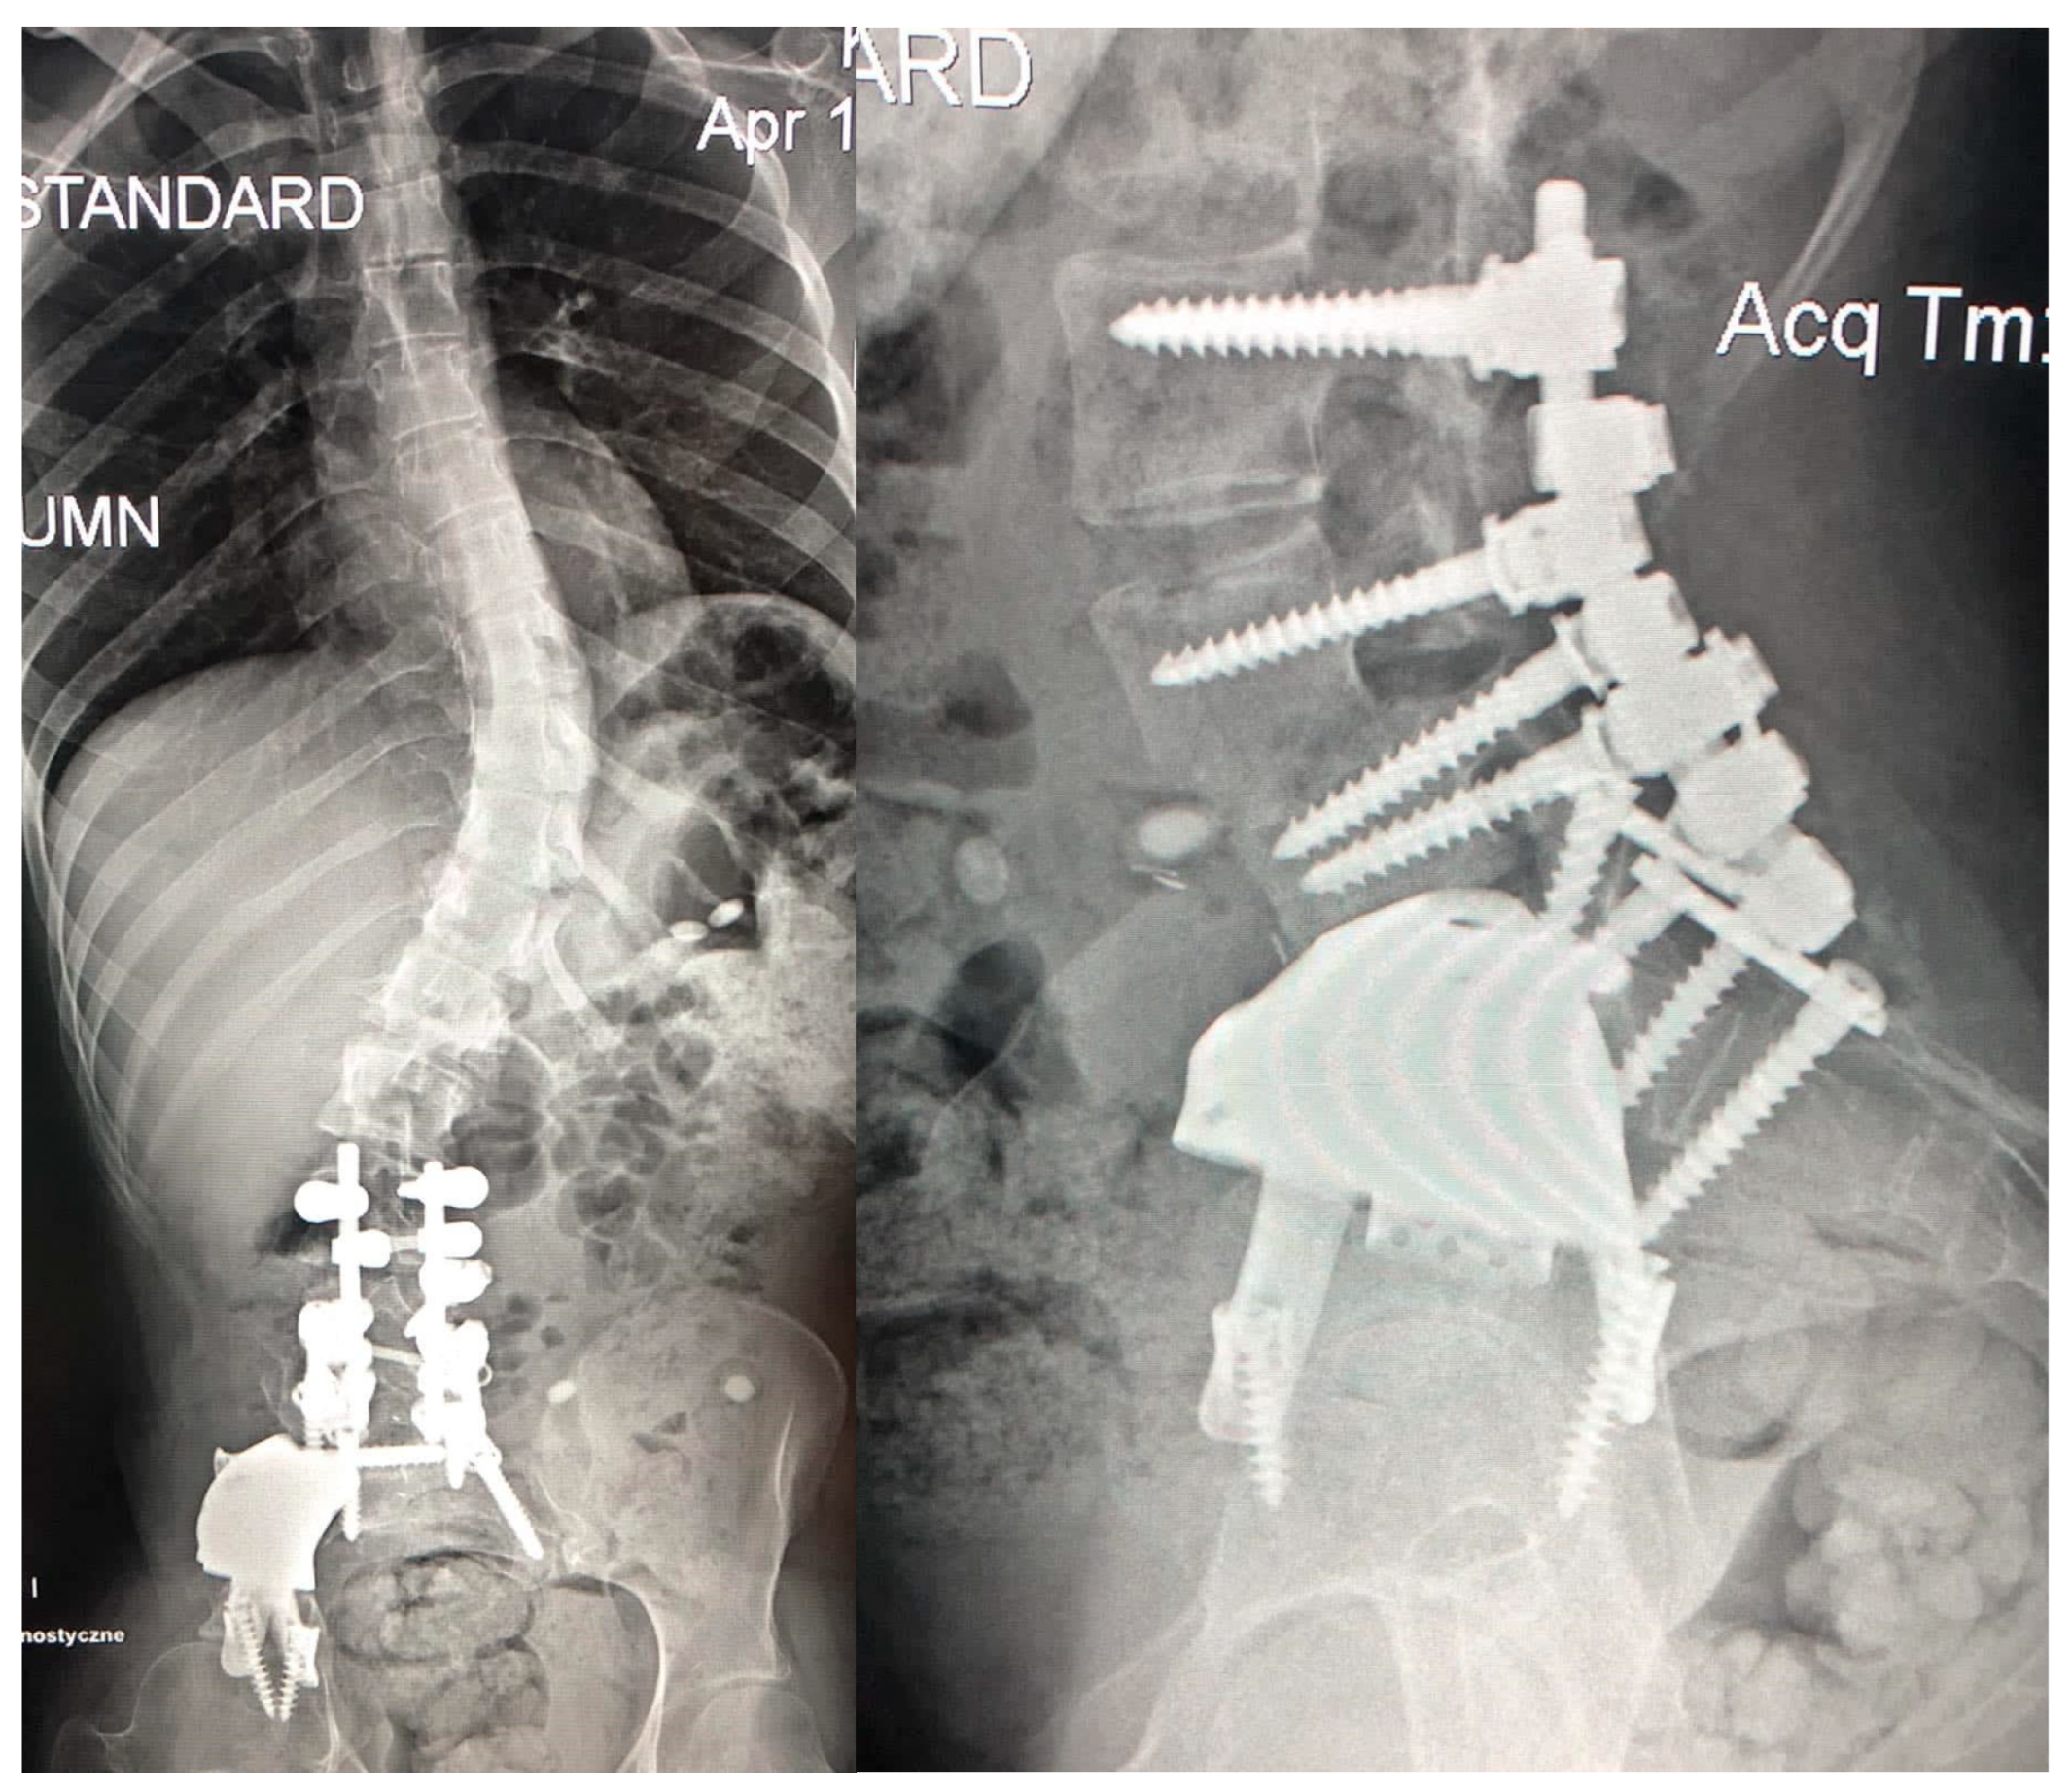

3.3.2. Spine Deformity